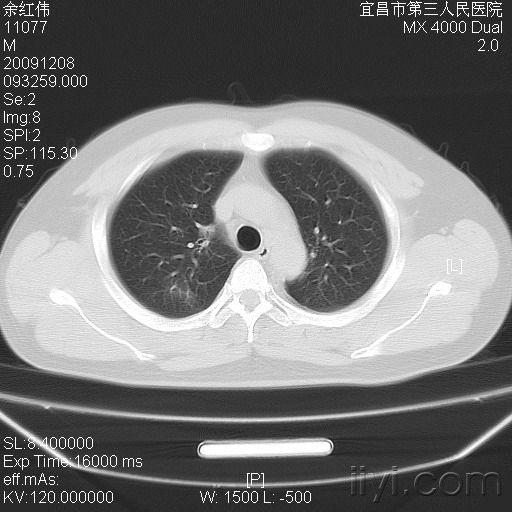

病例 1:同一小叶性肺炎患者于同日拍摄的胸片和肺 ct.

x线显示肺段或肺叶实变,或呈小叶样浸润,可有单个或多发的液气囊腔

沿肺纹理有模糊的斑片状阴影.肺纹理增粗,模糊.x线表现